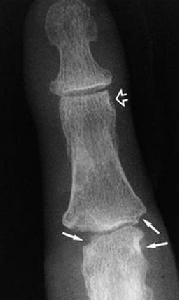

2.受累關節及胸部X線攝片、心電圖檢查。必要時行超聲心動圖檢查。

①每日關節晨僵至少1h(≥6周);②3個或3個以上關節腫(≥6,周);③腕、掌指關節或近端指間關節腫(≥6周);④對稱性關節腫(≥6周);⑤皮下結節;⑥手X線片改變;⑦類風濕因子陽性(滴度>1∶32)。具備4條或4條以上標準,可確診。